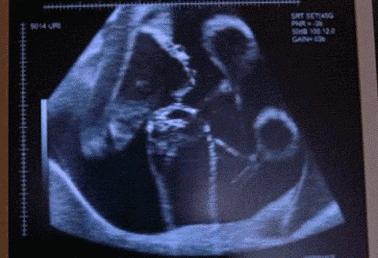

28岁的田女士与丈夫结婚已经6年了,记得在结婚那时,夫妻俩人就开始了造人计划并在不久就传来喜讯,可这样的欢乐没持续多久,在怀孕23周的时候,田女士肚子突然腹痛,并且阴道有出血的症状,家人赶紧把田女士送到医院,然而检查发现胎儿已经胎死腹中两周了。

这噩耗让夫妻俩难以接受,但是也无可奈何。直到一年后再次怀孕,为防意外再次出现,在得知怀孕后就辞职在家。可噩耗再次降临在她身上,宝宝又一次的胎死腹中,接一连二的打击让田女士崩溃了。

但是在给田女士做清宫手术时,发现她体内的指标有些异常,不仅血压高、甲状腺功能、血钾低,并且在怀孕后就出现皮肤紫纹、痔疮的症状,经一系列的检查,最终找到孩子死亡的原因—脑垂体微腺瘤。

医生表示脑垂体肿瘤一般是育龄妇女患上比较多,如果在得知患有脑垂体肿瘤的女性,一定要及时手术治疗。并且除了脑垂体微腺瘤的疾病使胎儿胎死腹中,孕妇在孕期也要注意这些隐患,才能保证宝宝的顺利降生。